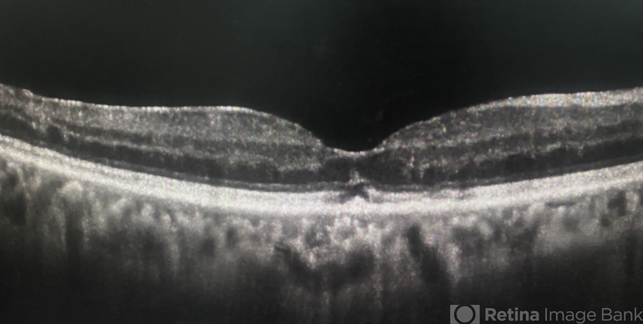

- macula, solar retinopathy, light toxicity

Optical coherence tomography system

Revo Optopol - Description

- OCT scan of a 65 year old male with a history of direct exposure to solar eclipse rays, visual acuity of affected eye 20/80, contralateral eye 20/25.